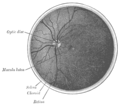

Cross-section of human eye, with choroid labeled at top.  | |

Interior of anterior half of bulb of eye. (Choroid labeled at right, second from the bottom.)  | |

المشيمية، المعروف أيضا باسم المشيمانية أو معطف المشيمية، هي طبقة الأوعية الدموية من العين ، تحتوي على الأنسجة الضامة ، وتقع بين شبكية العين و الصلبة . المشيمية البشرية هي الأكثر سمكاً في أقصى مؤخرة العين (عند 0.2 مم) ، بينما في المناطق البعيدة عن المركز تضيق إلى 0.1 مم.[1] توفر المشيمية الأكسجين والغذاء للطبقات الخارجية لشبكية العين . جنبا إلى جنب مع الجسم الهدبي والقزحية ، فإن المشيمية تشكل المسالك العنبية